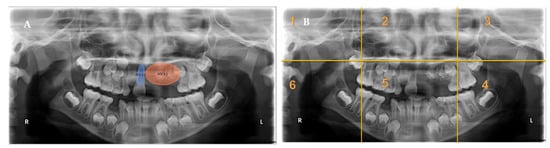

Figure 1 presents a heatmap of one single-involved-sextant radiograph and one multiple-involved-sextants radiograph. Heatmaps were generated to represent the areas with the longest fixations over time. The highest fixation density was on the AOIs, with minimal attention paid to the other areas of the panoramic radiograph. Residents fixated more on dentition than on bony structures.

Figure 1.

An example of a panoramic radiograph with areas of interest (AOIs) presented divided into sextants. (A) Panoramic radiograph with AOIs located in a single sextant presenting regional odontodysplasia, missing central incisor, and wide pulpal canal of tooth # 11. (B) Panoramic radiograph with AOIs located in multiple sextants presenting rudimentary second molars, odontogenic keratocyst, retained primary tooth, and missing lower permanent canine. (C) Divided sextants in a panoramic radiograph with AOIs located in a single sextant. (D) Divided sextants in a panoramic radiograph with AOIs located in multiple sextants. (E,F) Heatmap buildups from data registered for participants. (E) Postgraduate residents spent more time fixating on AOI located in one sextant than in other sextants. (F) Some AOIs had a considerably higher concentration of fixations than other AOIs. The colors of the heatmap range from a blue color, which indicates less fixation time, to a red color, which indicates a greater fixation time, all in milliseconds.